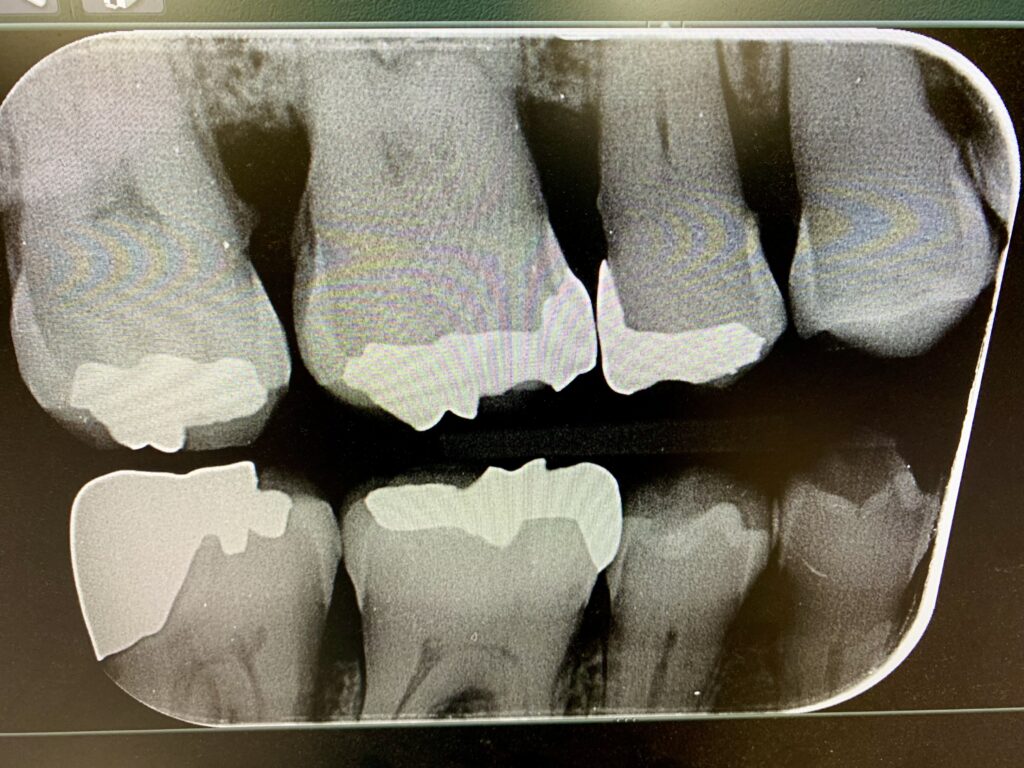

虫歯は「歯の間から進行する」ことが多いので、当院の診断では、拡大鏡での視診以外に、歯の間の診断ができるレントゲン撮影法【バイトウィング(咬翼法)】で撮ります。この撮影法の利点は、歯の間コンタクト部において精度の高い撮影ができること、また、その歯以外に対側の歯間も同時に診断できることです。

その結果、エナメル質内の虫歯の場合『PMTC』を施行して『フッ素塗布』を行います。象牙質まで進行した虫歯は、治療をします。

その治療は、できるだけ虫歯のみを削除し、即日で『光重合のコンポジットレジン充填』を行います。また、歯間の虫歯予防のために『デンタルフロス』の使用方法を説明します。

※当院患者様のレントゲンで、当該患者様本人より掲載許可は頂いております